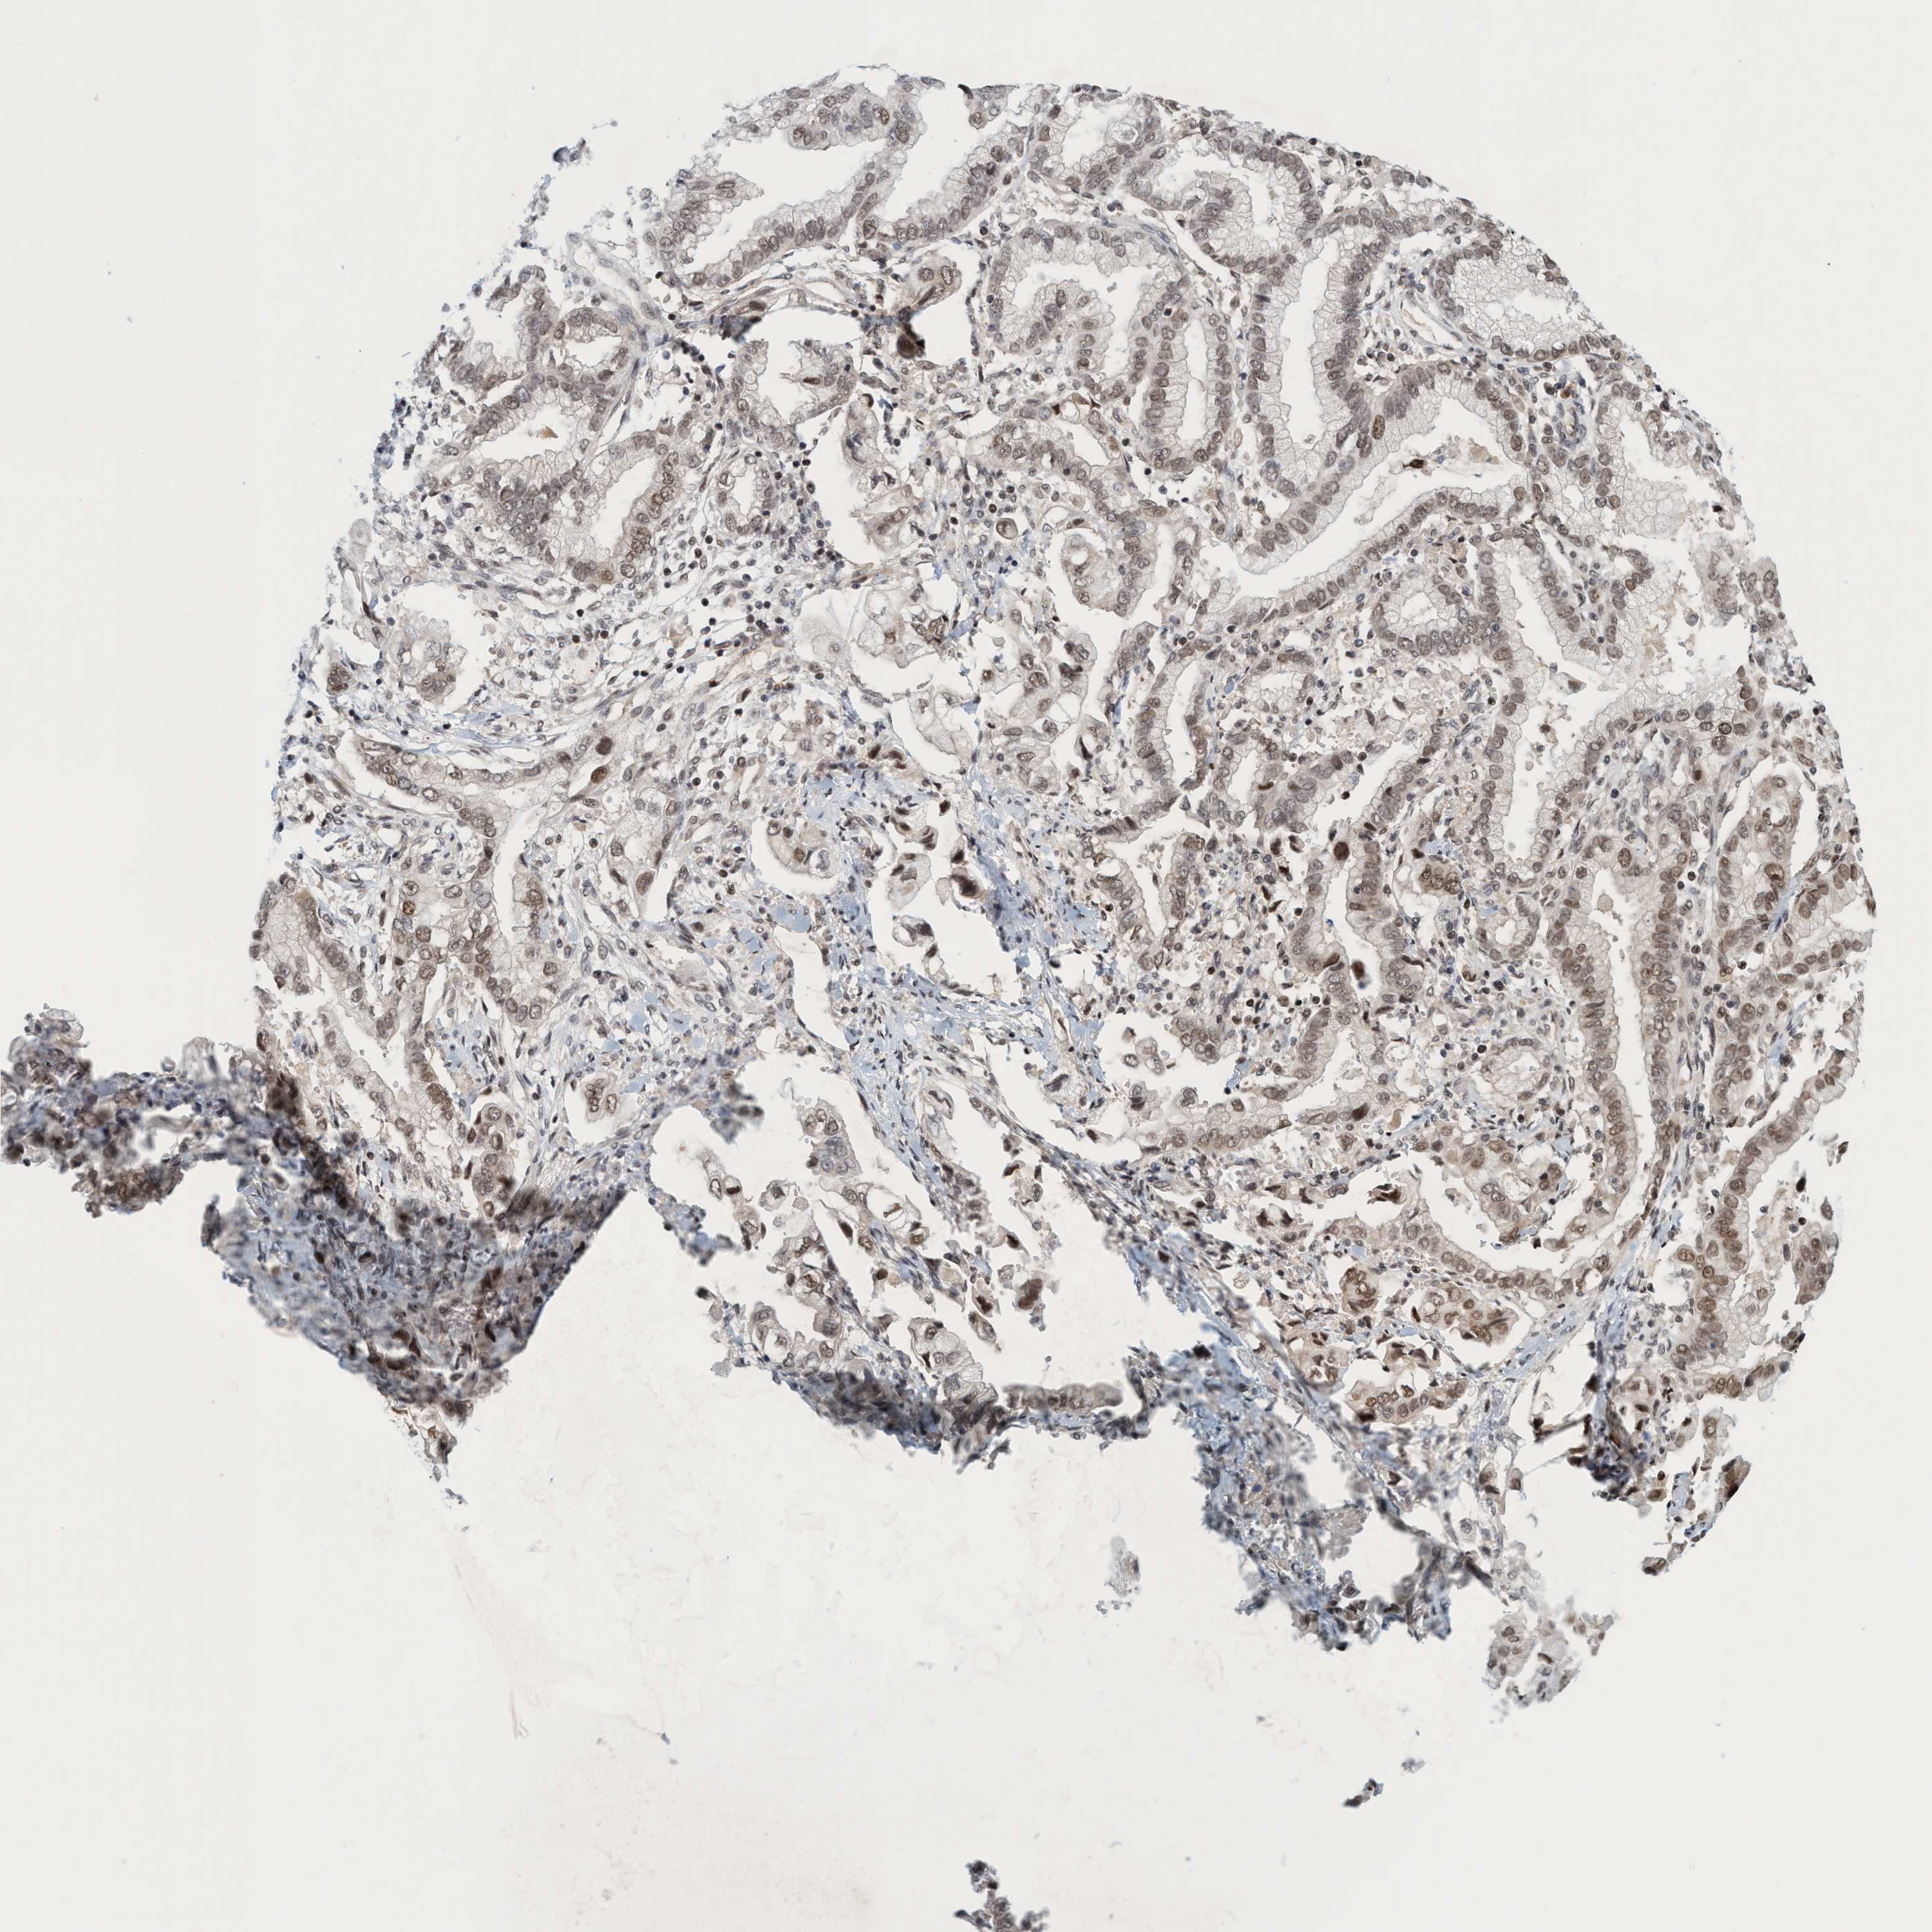

STOMACH CANCER - Protein expressioni

A mouse-over function shows sample information and annotation data. Click on an image to view it in a full screen mode. Samples can be filtered based on level of antibody staining by selecting one or several of the following categories: high, medium, low and not detected. The assay and annotation is described here.

Note that samples used for immunohistochemistry by the Human Protein Atlas do not correspond to samples in the TCGA dataset.

Antibody stainingi

Antibody staining in the annotated cell types in the current human tissue is reported as not detected, low, medium, or high, based on conventional immunohistochemistry profiling in selected tissues. This score is based on the combination of the staining intensity and fraction of stained cells.

Each image is clickable and will lead to virtual microscopy that enables deeper exploration of all samples and also displays staining intensity scores, fraction scores and subcellular localization as well as patient and tissue information for each sample.

Antibody HPA021557

Antibody HPA024646

Staining

High

Medium

Low

Not detected

Intensity

Strong

Moderate

Weak

Negative

Quantity

>75%

75%-25%

<25%

None

Location

Nuclear

Cytoplasmic/membranous

Cytoplasmic/membranous,nuclear

Adenocarcinoma, NOS